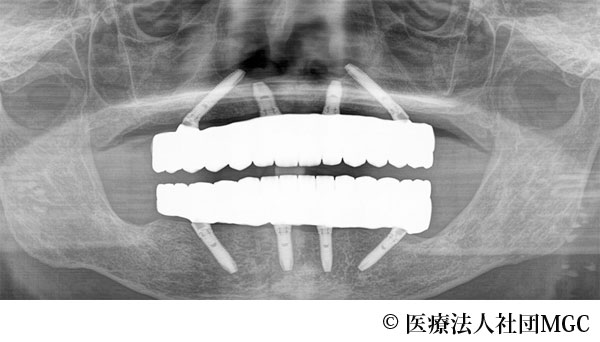

【症例1】上下All-on-4(オールオンフォー)

- 治療後

- 治療名

- 上下All-on-4(オールオンフォー)

- 費用

- 5,915,800円(税込)

- 期間

- 8ヵ月

治療内容

患者様の症状

歯がボロボロで食事が困難であるとご来院されました。

治療法

ご相談の結果、患者様の生活の質(QOL)を向上させ、しっかり噛めるように上下All-on-4(オールオンフォー)を行いました。

治療結果

機能性、審美性ともに改善し、満足していただけました。

※治療結果は患者様によって個人差があります。

治療を行う上での注意点(リスク・副作用)

インプラント周囲炎の可能性、まれに歯が欠ける可能性があります。